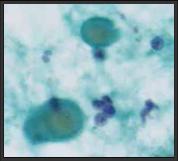

濃縮コロイドのよる組織推定

濃縮コロイド ⇒ 小濾胞内腔  ⇒ 小濾胞性濾胞腺腫